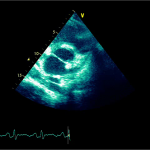

Ecocardiografia transtoracică

- Formaţiune hiperecogenă cu suprafaţa neregulată, care tapetează peretele liber al VD, grosime de 12 mm

- Dispusă de sub planul valvei tricuspide până in apropierea conului de ejecţie al valvei pulmonare

- SIV aplatizat

Ecografia transesofagiană:

Confirmă datele de la ecografia transtoracică